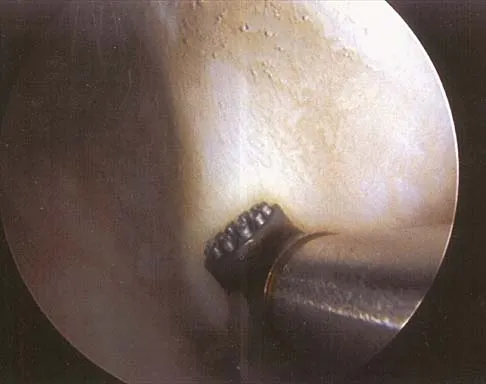

What neurovascular structure is in closest proximity to the probe in the arthroscopic view of the elbow shown in Figure 50?